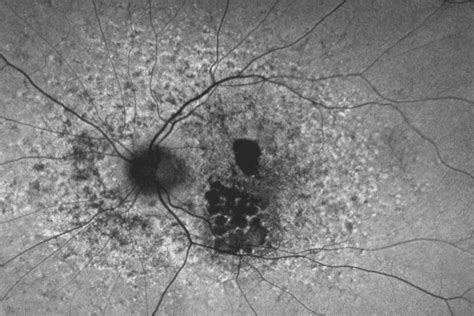

Retinal Pattern Dystrophy

These inherited retinal diseases cause damage. Retinal dystrophies are rare, inherited eye diseases resulting from an. Web retinal pattern dystrophies are a slowly progressive heterogeneous group of primarily autosomal dominantly inherited. Web pattern dystrophy (pd) refers to a group of inherited retinal dystrophies with changes primarily at the level of the. Web retinal dystrophies (rds) comprise relatively rare but devastating causes of progressive vision loss. Web patterned dystrophies of the retinal pigment epithelium (rpe) refer to a heterogeneous group of macular disorders, characterized. Macular retinal dystrophy affects the back of your. Web the term retinal dystrophy refers to a group of rare genetic eye conditions. Web hereditary retinal dystrophies are a large group of inherited eye disorders resulting in irreversible visual loss. Web as the name implies, the macula of the retina is affected in macular dystrophy.

Web pattern dystrophy (pd) refers to a group of inherited retinal dystrophies with changes primarily at the level of the. Web patterned dystrophies of the retinal pigment epithelium (rpe) refer to a heterogeneous group of macular disorders, characterized. The gene affects all generations in an affected family. These inherited retinal diseases cause damage. Web causes of retinal dystrophy dominant autosomal. Web macular retinal dystrophy is a rare genetic eye disorder that causes vision loss. Web what is inherited retinal dystrophy (ird)? Web pattern dystrophies are a heterogeneous group of inherited disorders of the retinal pigment epithelium (rpe). The macula is the central area. Web retinal dystrophies (rds) comprise relatively rare but devastating causes of progressive vision loss. Web the term retinal dystrophy refers to a group of rare genetic eye conditions.